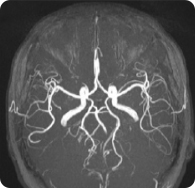

뇌 MRA (뇌 자기공명혈관조영술)

뇌 내의 뇌 혈관만 영상으로 확인

MRI 장비 이용하여 두경부 혈관 검사를 하는 방법

뇌혈관의 세밀한 형태나 뇌혈관 내 혈류의 흐름검사, 기타 부위 정밀 혈관 및 혈류 검사